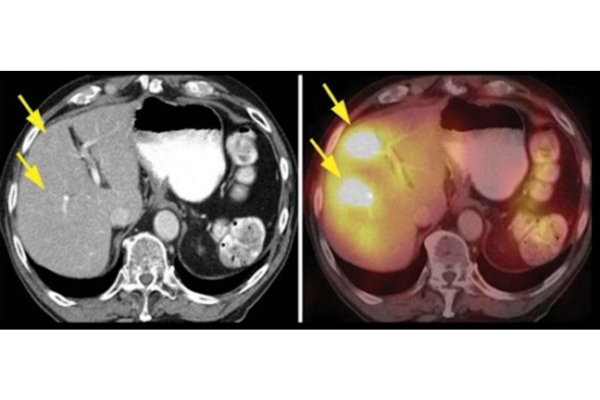

Gan là một cơ quan có tốc độ chuyển hóa rất cao, nên rất nhạy cảm với các tổn thương thiếu máu. Tế bào gan có thể bị thiếu máu bởi nhiều biến cố khác nhau, có thể là một tình trạng làm giảm tưới máu hệ thống như choáng hay ngừng tim; hoặc là những biến cố gây gián đoạn cấp máu cục bộ một hay nhiều nhánh động mạch gan. Tổn thương gan do các biến cố làm gián đoạn cấp máu cục bộ động mạch gan như vậy gọi là nhồi máu gan - có các đặc điểm rất riêng về bệnh học, cũng như là chẩn đoán và điều trị.